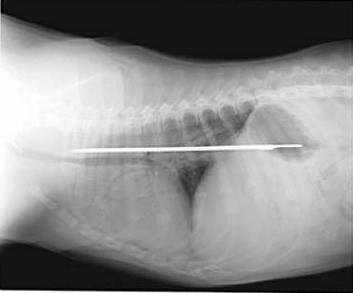

11. Anjing penelan pisau

Seekor Saint Bernard menelan pisau 13-inch pada tahun 2005. Dia baik-baik saja setelah operasi dan kejadiannya hanya meninggalkan bekas luka 8-inci.